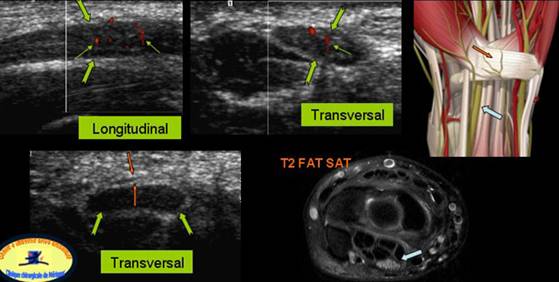

Patologic, semiologia ecografica este in functie de stadiul anatomo-patologic.

Entezopatia

Entezopatia simpla se prezinta sub forma unei tumefactii edematoase a tendonului cu pierderea organizarii fibrilare. Se asociaza frecvent cu o hiperemie la doppler color ceea ce traduce o angiogeneza

Aceasta entezopatie poate lua un aspect nodular cu aparitia unei zone de degenerescenta mucoïda care poate evolua spre o veritabila desirare intratendinoasa care apare sub forma unei disectii lamelare. Acest clivaj se poate intinde pana la insertia ligamentului colateral lateral. Tendonul poate fi sediul unei dezinsertii partiale uneori asociate cu o decolare a periostului. Poate surveni chiar o veritabila dezinsertie completa a tendonului comun.